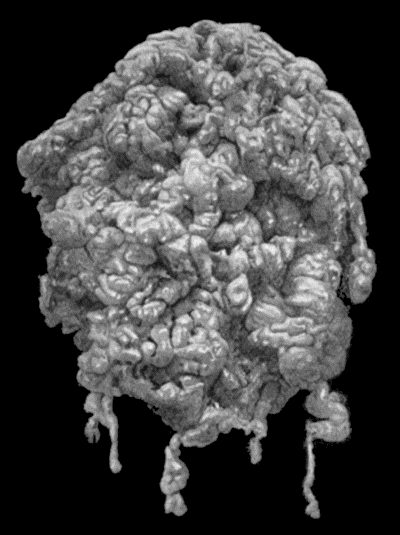

168.Multiple partially ossified Chondromas of Synovial Membrane from Shoulder-joint 542

76.Congenital Cystic Tumour or Hygroma of Axilla 328